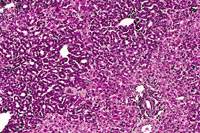

Multiple biliary and hepatocellular hyperplastic and neoplastic lesions in the liver of a 4-week-old transgenic mouse.

Confluent biliary and hepatocellular neoplasms totally occupying the left liver lobe of a 4-week-old transgenic mouse.